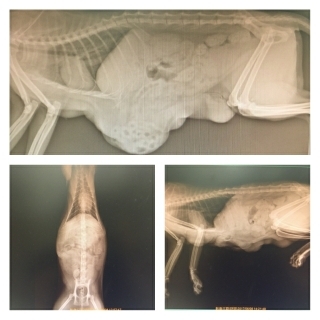

主題: 胸部腫大的黑媽 申請者姓名: 簡蕙瑱 花色: 申請日期: 2017-07-02 13:19:08 申請者部落格: 申請者臉書網址: https://m.facebook.com/home.php?_rdr 所在縣市/合作醫院: 花蓮縣/美崙動物醫院 治療費用: 9400元 需求人數: 22人 已結案 (2024-06-01 13:26:46) 報名人員: Noel6731(已付款)、show x2(已付款)、Carambar Liu(已付款)、林小豬(已付款)、Yvonne x2(已付款)、Yating Yeh、Rachel Hsieh x2(已付款)、SY Liou(已付款)、Emily Yen x2(已付款)、Shan Chou x9(已付款)、JasmineC(已付款)、 候補人員: 動物病情說明: 這區貓咪一直都持續在進行TNR,剛好同事住在附近,有聽同事提過似乎看過一隻貓肚子腫大,懷疑是否長腫瘤,只是一直沒有遇過,因為那區的貓咪是會進去附近的市場覓食,而且會有路過的民眾放置廚餘,但是那區的居民對貓咪極不友善,也遇到民眾刁難,所以餵食的時間總是在夜深人靜時,貓咪也許是因為被驅趕過,所以貓咪的警覺性比其他餵食區還強烈,在六月初時,連續兩個星期在這區進行TNR,終於誘捕到這隻貓咪,緊急送醫後,醫生先檢查,照超X光片,才發現原來腫大是因為疝氣造成的,而且已經有腸子掉落其中,怕是放回後會有更多的器官陷落,所以評估後,醫師建議開刀手術並留院觀察傷口復原的狀況。

住院前幾日,每日用藥並注射長效抗生素,貓咪每日都正常進食,所以傷口復原的狀況良好。

之後的狀況都良好,癒合極佳,術後的X光片看起來器官都已在原位置,沒有再產生變動,住院兩週就拆線,原定放回。動物近況說明: 放回後每日都會出現在餵食區等待,活力食慾都正常,感謝大家幫忙讓貓媽可以恢復健康,也免於生生不息的命運,衷心感謝協會和大家的協助,感激不盡。